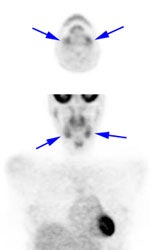

Brown Fat: Prominent, symmetric supraclavicular tracer uptake was seen in this patient without a corresponding CT finding. Uptake in this area has been felt to be related to the presence of "brown" fat. |

|

|